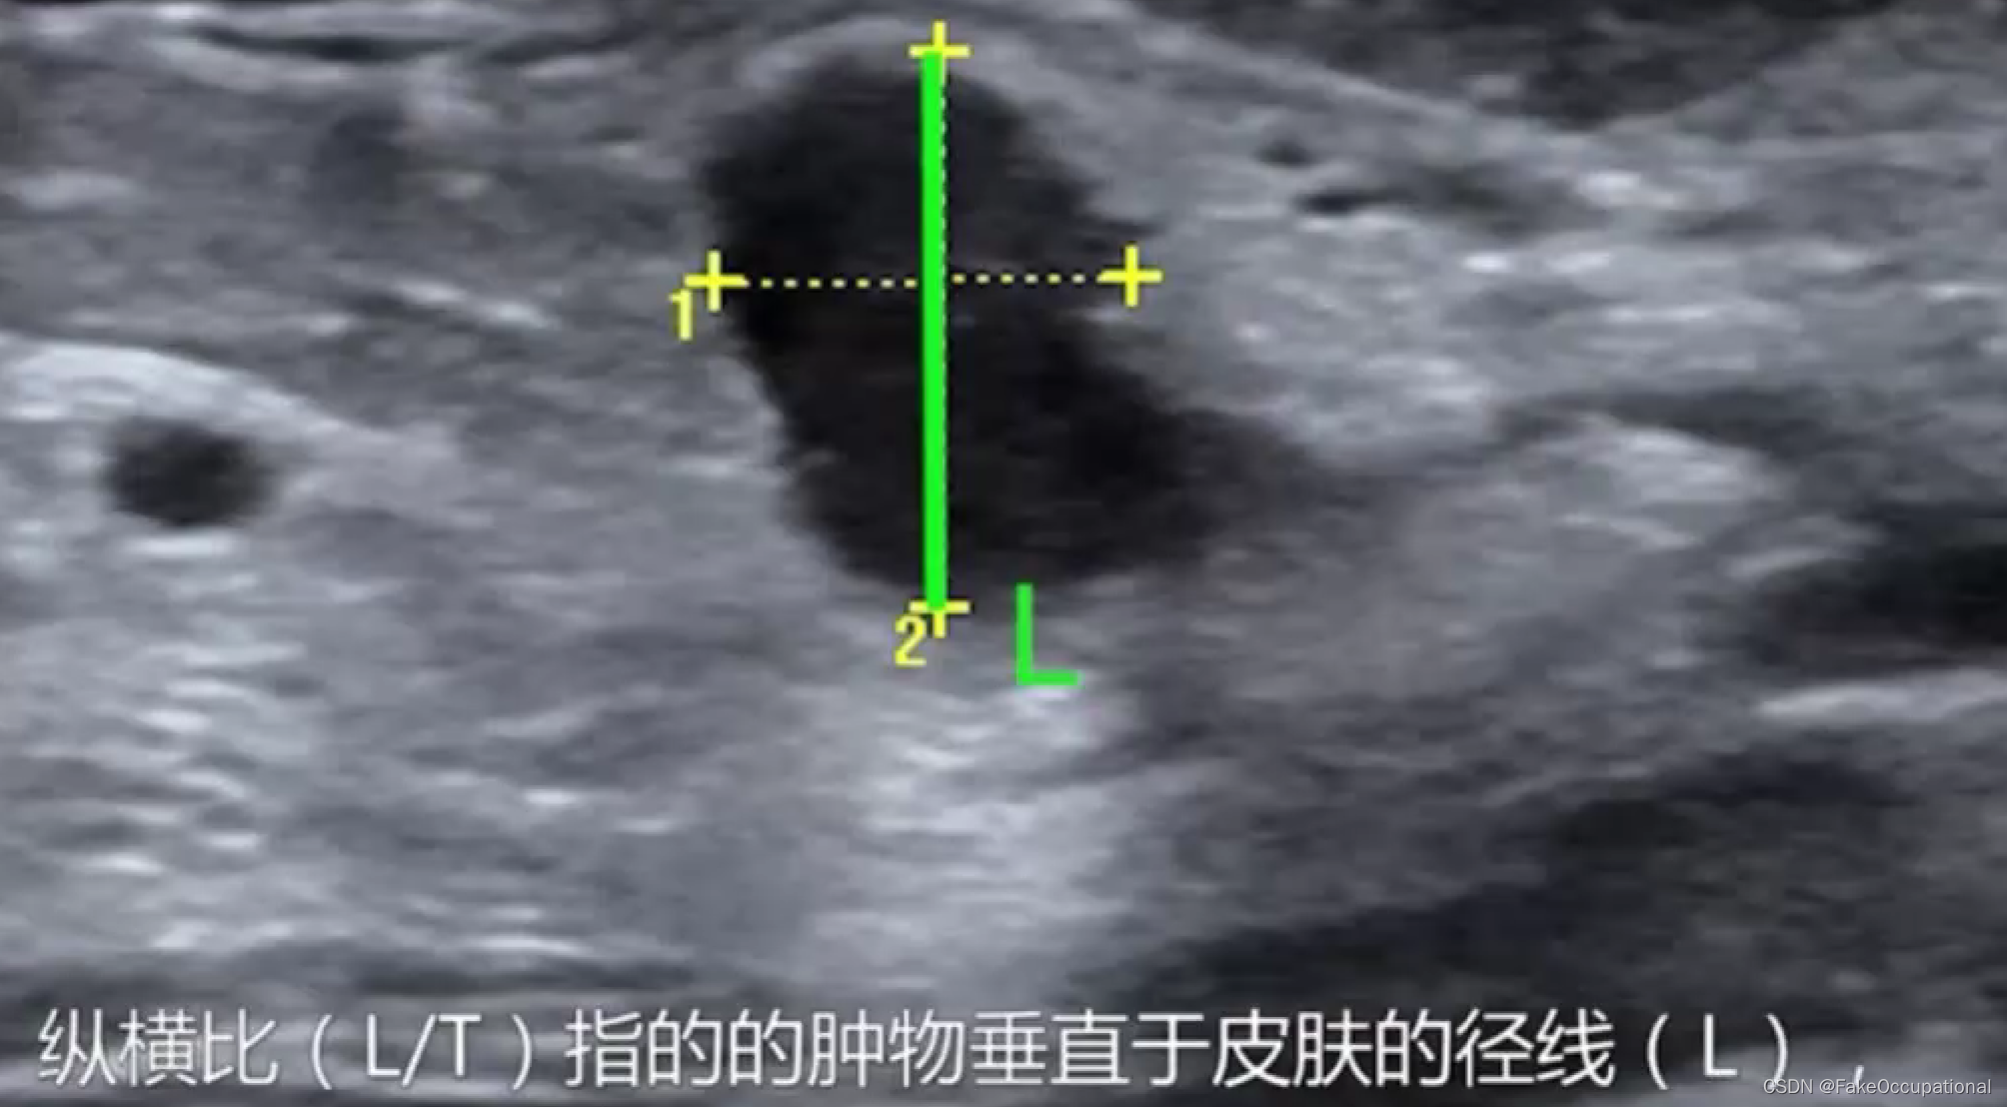

乳腺癌

- 患者18岁,微小癌

- 其理论依据是恶性肿瘤常星离心性生长